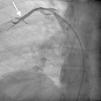

Case reportA 44-year-old man presented with several weeks of palpitations. He also described symptoms of dyspnea with mild exertion and substernal chest discomfort at rest. He had a history of long-standing systemic hypertension. The 12-lead ECG showed atrial fibrillation with rapid ventricular rate. His 2D Doppler echocardiogram revealed a mildly enlarged RA and right ventricle (RV). He subsequently underwent right and left heart catheterization with selective coronary angiography. Right and left heart catheterization with a full oximetry run to calculate shunts revealed Qp/Qs of 1.3. Selective coronary angiography was performed using right radial artery access, and showed no significant coronary disease. However, angiography of the aortic arch showed a single trunk takeoff for the large vessels from the aortic arch (Figure 1). Using right femoral vein access, a 5-Fr multipurpose diagnostic catheter was advanced into the upper (Figure 2) and middle (Figure 3) right pulmonary veins as they opened into the superior vena cava (SVC). To exclude any possible associated atrial septal defect, an MP-1 catheter was engaged into what proved to be a coronary-cameral fistula (CCF) opening into the RA separately from the coronary sinus (Figure 4), the CCF went from the coronary vein to the RA and the coronary sinus was also filled with contrast retrogradely from the vein (Figure 4). Pulmonary angiography using a 5-Fr pigtail catheter showed a moderately dilated pulmonary trunk (Figure 5). Following consultations with the cardiothoracic surgery and pediatric cardiology teams, it was felt that the best course of management would be to follow the patient clinically with serial echocardiography, as there was no significant right-to-left shunt.

Our patient had a venous CCF draining into the RA from the coronary vein in addition to the right upper and middle pulmonary veins draining through the SVC. There is no previously reported case of SS associated with venous CCF in the literature. Coronary-cameral fistulas are unusual congenital or acquired anomalous communications between an epicardial coronary artery and a cardiac chamber: the RA, coronary sinus, right ventricle, left atrium, or left ventricle. In a review of 304 patients with CCF and coronary vascular fistula (CVF), a continuous cardiac murmur was heard in 82% of the subjects. Dyspnea, chest pain and angina pectoris, palpitations, and fatigue are reported symptoms in clinical presentations. Although rare, infective endocarditis has been reported in patients with CCF, but not in those with CVF.12